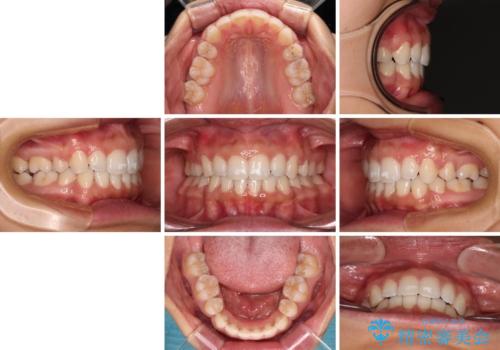

2年から2年半の治療期間を想定しており、予定通りの期間で無事に終了することができました。

唇や顎先に力を入れないなくてもスムーズに唇を閉じることができるようになりました。